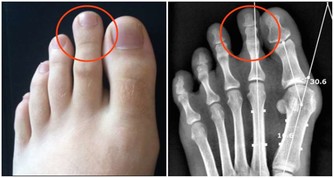

張大伯幾年前做了心臟支架手術,每天都要服用阿司匹林,就這樣吃了很長時間,他突然發現自己的腳趾關節疼痛難忍,還有點發紅,自己也沒犯飲食忌諱,怎麼痛風發作了呢?家人趕緊帶張大伯到醫院檢查。

相信大家都不想痛風發作,不僅是因為那滋味太痛苦了,還因為它會帶來各種並發症,比如說關節疼痛,嚴重的甚至會變形,不能正常活動關節。若是尿酸結晶沉積在腎小管裡,還有可能損傷腎臟,形成結石,給身體加上另一重痛苦。